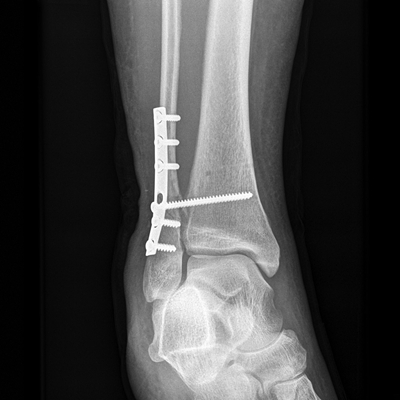

骨折圖片